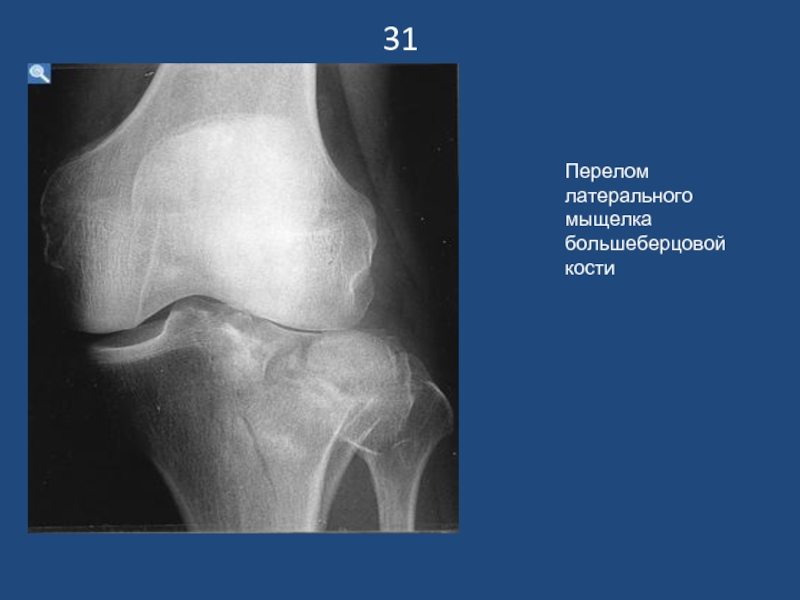

Слайд 3231

Перелом латерального мыщелка большеберцовой кости